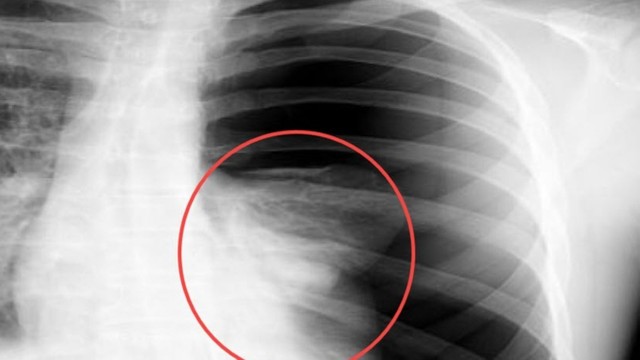

Tràn khí màng phổi là tình trạng khí lọt vào khoang màng phổi, gây xẹp phổi một phần hoặc toàn bộ. Đây là bệnh lý có thể xảy ra đột ngột và đe dọa tính mạng nếu không được xử lý kịp thời. Vậy tràn khí màng phổi có chữa được không?